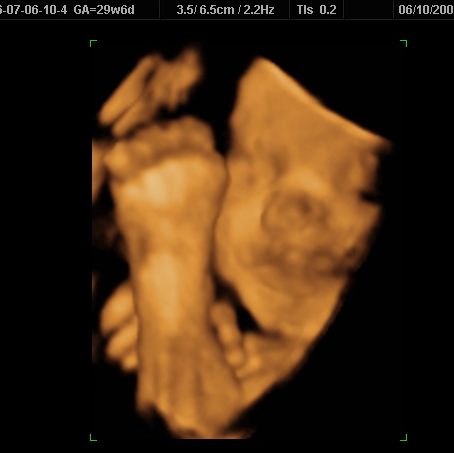

3d/4d sono yesterday w/pics...

I had it done at Impact. The baby wasnt really in the best position, so it was hard to get good shots of him, but it was still a great experience...

Image Attachment(s):